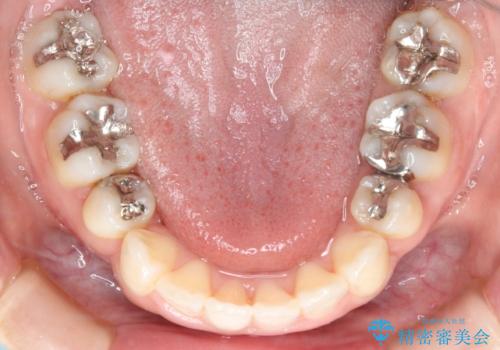

- 歯のガタつきと出っ歯が気になるので矯正治療を希望し来院された患者様です。

上下顎とも歯を並べられるスペースが無く、口元を下げたいというご希望だったので、抜歯とワイヤー矯正を併用した治療を計画しました。

抜歯スペースを利用し口元を大きく下げることが出来ました。